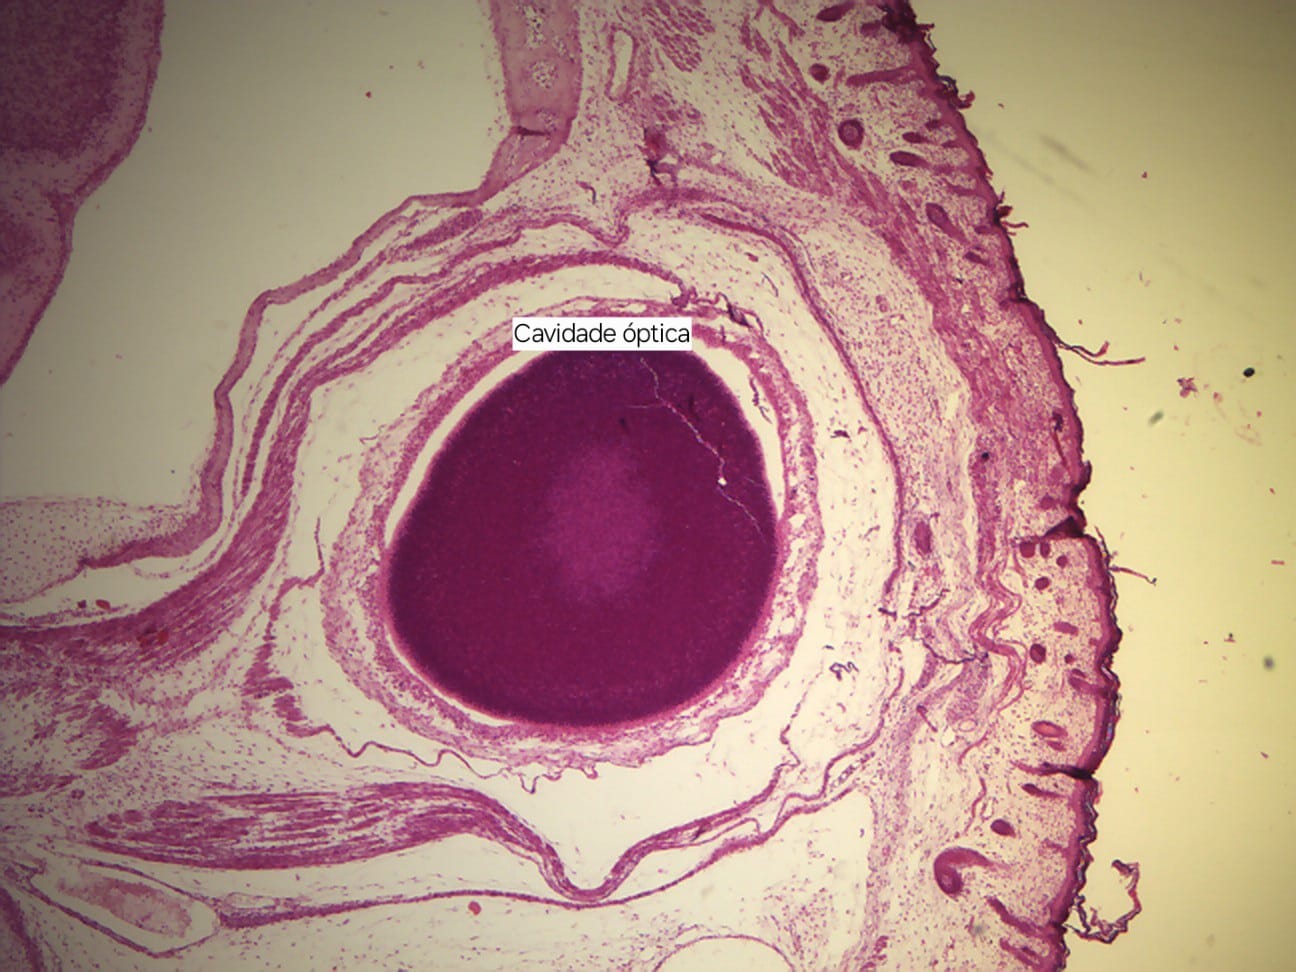

Imagens Embriologia da Face